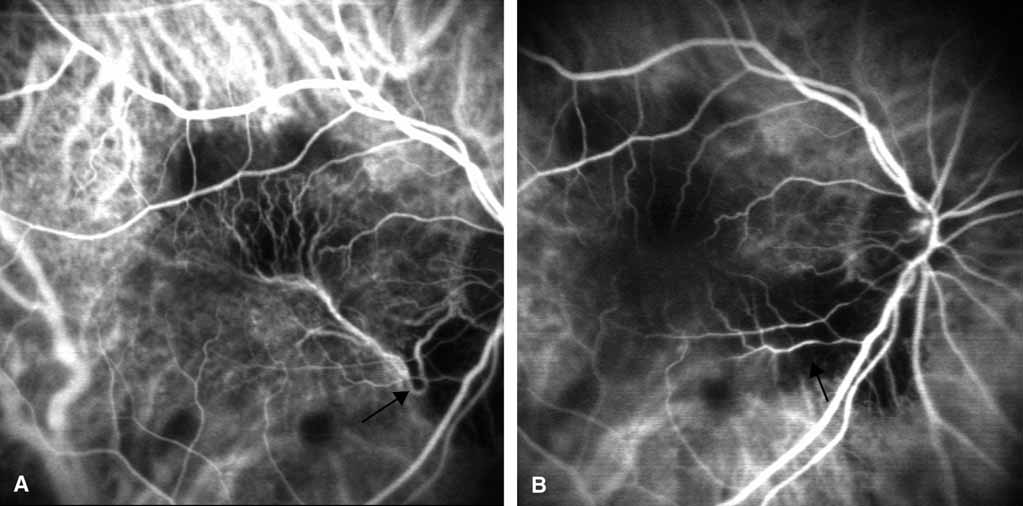

PATHOPHYSIOLOGY OF CHOROIDAL NEOVASCULARIZATION In AMD, it has long been postulated that focal choroidal ischemia may play a role in the development of CNV. Macular choroidal vascular “watershed” zones have been known to exist, but their causal relationship to CNV has never been determined. On ICG angiography, these presumed watershed zones appear as areas of relative, abnormal hypofluorescence in the early phases of the angiographic study.44 A published ICGA analysis by Ross et al.45 revealed a much higher incidence of the presumed watershed zones in the macula of eyes with AMD compared with age-matched control eyes (55% vs. 15%, respectively). Furthermore, Goldberg et al.46 found that 92% of eyes that developed choroidal neovascular membranes had watershed zones. These data support the notion that watershed zones play a role in CNV development and that ICG angiography may be useful once again in identifying eyes at the highest risk for the exudative transformation. Other studies have shown that ICGA can distinguish the different types of drusen and, therefore, may be useful to evaluate the risk of progression of AMD.47 CLASSIC CHOROIDAL NEOVASCULARIZATION Classic CNV as determined by FA shows a similar appearance on ICGA with well-defined hyperfluorescence throughout the transit phase and leakage obscuring the borders of the lesion in the late frames. However, the leakage in the late frames tends to be less pronounced with ICGA. Overall, ICGA offers no advantage over fluorescein angiography in this setting. OCCULT CHOROIDAL NEOVASCULARIZATION Occult CNV assumes a variety of FA patterns.48 There can be obscuration of the neovascularization from fluorescein blockage by overlying fluid or pigment or from rapid leakage of the dye in the area of interest. Sometimes there is slow, irregular fluorescein leakage with poorly delineated borders. With occult CNV, there may be varying degrees of uncertainty as to the precise location and extent of the choroidal neovascular membrane using FA alone. Both fluorescein and ICG dyes appear to be retained by CNV and will, therefore, exhibit hyperfluorescence relative to surrounding tissue.1 ICGA theoretically provides enhanced visualization of CNV in this setting because the ICG infrared fluorescence better penetrates pigment and fluid than the visible light fluorescence of sodium fluorescein, and the highly protein-bound ICG dye leaks less from abnormal vessels compared with fluorescein dye as described earlier. Several patterns of ICG hyperfluorescence for occult CNV have been observed.4,11,49,50 These include early-appearing small hyperfluorescent spots (hot spots), plaque-like hyperfluorescence, collections of abnormal vessels, and late-appearing hyperfluorescence with indistinct edges (Figs. 3, 4, and 5). A combination of these patterns can be seen. Although thin blood is easily penetrated by the infrared fluorescence (Fig. 6), thick blood will still obscure the underlying choroidal pattern to some degree. Reichel et al.51 demonstrated that ICGA was superior to fluorescein angiography in determining the extent of CNV secondary to age-related macular degeneration obscured by hemorrhage. Several investigators have demonstrated the ability of digital ICG angiography to not only confirm, but also better delineate CNV in certain cases of exudative AMD.1,3,4,10–13,33 Early large series by Yannuzzi et al.4,52 and Regillo et al.,11 using digital videoangiogram systems demonstrated well-defined hyperfluorescent foci of ICG presumably corresponding to the entire choroidal neovascular process in approximately 40% of cases, where FA revealed occult or ill-defined CNV only (see Figs. 3, 4, 5, and 6). A similar yield was reported early on by Kuck et al.,13 using SLO-based ICGA. Furthermore, studies by Regillo et al.,11 Sorenson et al.,53 and Guyer et al.54 have shown that laser photocoagulation of well-defined ICG hyperfluorescent foci with treatment guided solely by the ICGA findings resulted in short-term resolution of exudation and stabilization or improvement of vision in 56% to 69% of cases. Although prior studies with AMD patients have shown that occult or ill-defined CNV on FA have, in general, a poor visual prognosis,55,56 adequate controls are not available to determine whether laser therapy as outlined in these studies significantly altered the natural history. Nonetheless, the data suggest that treatment based on ICGA findings may result in prompt resolution of exudation and improved visual acuity in selected cases. Therefore, this technique has the potential to increase the yield of exudative AMD cases that may be effectively managed by conventional laser photocoagulation treatment methods. SERIOUS PIGMENT EPITHELIAL DETACHMENTS In contrast to the bright hyperfluorescence on FA, serous pigment epithelial detachments most often appear either isofluorescent or slightly hypofluorescent; associated hyperfluorescent CNV is, therefore, more easily seen on ICGA (Fig. 7). In AMD, a serous pigment epithelial detachment (SPED) is usually associated with CNV. However, the CNV may not be adequately visualized with fluorescein angiography because of rapid fluorescein pooling into the sub-pigment epithelial space. With ICGA, the neovascular component shows a relative hyperfluorescence, whereas the serous component of the complex is isofluorescent or hypofluorescent due to the minimal amount of ICG leakage(Fig. 7) It was initially hoped that this would lead to an increased yield of successful laser treatment of such lesions. Baumal et al.57 demonstrated that ICGA revealed CNV associated with SPED in 83% of eyes in which the CNV was not well delineated by fluorescein angiography. However, laser treatment to the presumed neovascular focus as guided by the ICGA findings did not change the visual outcome compared to controls. Lim et al.58 showed a transient stabilization of visual acuity following ICGA-guided laser photocoagulation for CNV associated with SPED. However, the treatment benefit diminished with time. The collective experience of Retina Service members at Wills Eye Hospital indicate that most eyes with SPED do not seem to benefit from treatment, although there are occasional dramatic, favorable results. This is especially true if the neovascularization on ICG angiography is small and located at the edge (rather than within) of the SPED.44 PRE– AND POST–LASER TREATMENT ICGA may be a useful adjunct to FA in determining the presence or extent of recurrent CNV.4,11,53 Photocoagulated areas on ICGA are completely hypofluorescent, and, compared with FA, there is greater contrast between the photocoagulated site and any associated persistent or recurrent CNV (Fig. 8). Preliminary data reveal a good correlation between treatment success and the lack of any residual abnormal ICG hyperfluorescence, indicating that the ICGA may accurately identify the presence of CNV.11,53 This is further supported by a human clinicohistopathologic study in which a well-delineated plaque of hyperfluorescence on the ICGA corresponded precisely with abnormal subretinal pigment epithelial fibrovascular tissue identified by histopathologic examination of serial sections.59 Regillo et al.60 evaluated persistent and recurrent choroidal neovascularization and found ICGA to improve visualization of ill-defined choroidal neovascular complexes seen on fluorescein angiography. However, ICGA was not useful when evaluating post-treatment fluorescein angiograms negative for any CNV or when the FA showed well-defined CNV. ATYPICAL NEOVASCULAR MACULAR DEGENERATIONS Idiopathic Polypoidal Choroidal Vasculopathy Polypoidal choroidal vasculopathy is a form of CNV with recurrent subretinal and sub-RPE serosangiousmacular detachments. The condition originally was thought to occur mainly in African-American women ages 40 to 80 years who are hypertensive or diabetic.61 However, recent studies have found this condition in Caucasian and Asian patients.62 IPCV demonstrates branching inner choroidal vessels with terminal aneurysmal-like dilatations. These lesions are most commonly found in the peripapillary region. However, isolated lesions can also be found in the macula or peripheral fundus.63IPCV appears as early, intense unilateral or multifocal hyperfluorescent “hot spots” on ICGA. The late phase of the ICGA shows a washout from the center of the polypoidal lesion with staining of the surrounding choroidal vasculature64–70 (Fig. 9) We have used ICGA to aid in the diagnosis of a case of presumed idiopathic polypoidal choroidal vasculopathy.64,65 The characteristic multiple, saccular aneurysmal-like dilatations in the choroid were readily apparent under associated blood and exudate (Fig. 12). Conventional thermal laser photocoagulation of these choroidal vascular anomalies can lead to resolution of the exudative manifestations, and the ICGA may serve to guide treatment analogous to localizing and directing laser treatment in selected cases of exudative macular degeneration.63 Successful treatment of IPCV lesions with photodynamic therapy has also been described.71 Retinal Angiomatous Proliferation Retinal angiomatous proliferation (RAP) is a form of neovascular AMD in which the neovascularization appears to originate in the inner retinal layers then extends into the subretinal space, sometimes leading to a retinal-choroidal anastomosis. RAP lesions have a well-defined retinal–retinal anastomosis between the normal retinal vasculature and deep retinal vascular complex. With conventional fundus-camera based ICGA, RAP lesions show intense focal hyperfluorescence (hot spot) corresponding to the intraretinal neovascular focus. The lesion becomes more hyperfluorescent in the mid and late phases of the ICG as the dye leaks intraretinally.72 With SLO-based ICGA, both retinal feeding and draining vessels are often readily identified. RAP lesions are most easily detected when associated with a SPED with a background of ICGA hypofluorescence (Fig. 10) Identification of early stage RAP lesions may allow for successful treatment by a variety of approaches, such as conventional thermal laser treatment, photodynamic treatment (PDT), or surgical ablation of the anastomotic retinal vessels.73,74 Choroidal Feeder Vessel Treatment Using SLO-based ICGA, investigators have been able to identify choroidal “feeder” vessels of AMD-related subfoveal choroidal neovascularization. The SLO allows for rapid image acquisition with rates of up to 20 frames per second. This allows for differentiating choroidal arteries from veins, which is not possible with fundus camera-based ICGA. Using SLO–ICGA and concentrating on the early choroidal filling phase, investigators have been able to identify choroidal vessels that directly feed CNV in selected cases (Fig. 11) Treatment of these “feeder” vessels with laser photocoagulation may or may not result in long-term involution of CNV.75–79 Further study with this treatment approach is needed. MISCELLANEOUS MACULAR DEGENERATION STUDIES Studies have suggested that ICGA may have predictive value for the development of CNV in AMD. Different groups of investigators have found that eyes known to have dry AMD with only drusen and alterations in the retinal pigment epithelium and no leakage on fluorescein angiography occasionally harbor ICG hyperfluorescent plaques. The plaques were discovered incidentally in patients in whom the fellow eyes had active exudative signs. By following these patients over time, it was determined that the eyes that were clinically dry with ICG hyperfluorescent plaques were much more likely to develop exudative manifestations than dry AMD eyes without ICG abnormalities.80,81 Therefore, in people with dry AMD in one eye and a history of CNV in the fellow eye, the presence of incidental, abnormal ICG hyperfluorescence in the “dry” eye may be a predictive indicator of future exudative changes in that eye.44 |